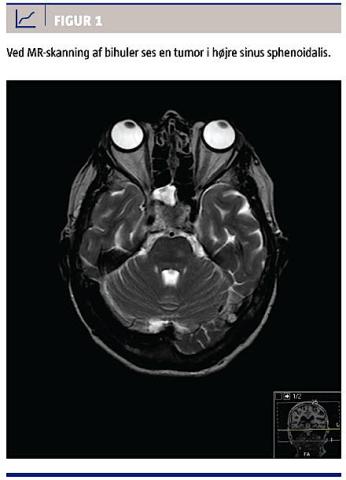

Fra ambulatoriet blev patienten senere indlagt til observation for hjernemetastaser pga. nytilkommen diplopi samt højresidig facialis- og abducensparese. Blodprøver viste cancerantigen (CA)-19,9 > 32.000 10E3arb. e./l og CA-125 335 10E3arb. e./l. En UL-skanning af leveren viste tumorsuspicio i højre og venstre leverlap. En CT af thorax og abdomen viste levertumor og retroperitoneale metastaser. CT’en af cerebrum var uden patologi, men en MR-skanning af cerebrum viste en patologisk proces i højre sinus sphenoidalis og ala minor samt ossøs destruktion op mod sinus cavernosus (Figur 1).